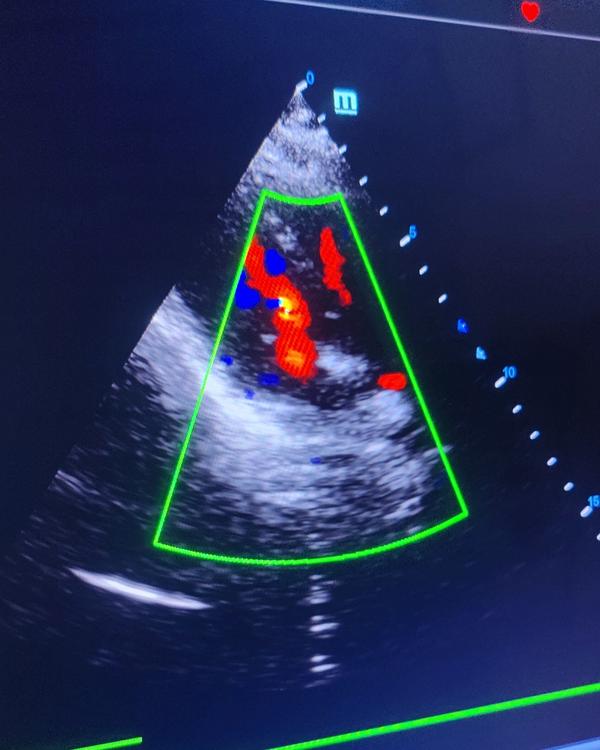

Image Gallery

Pictures That Speak